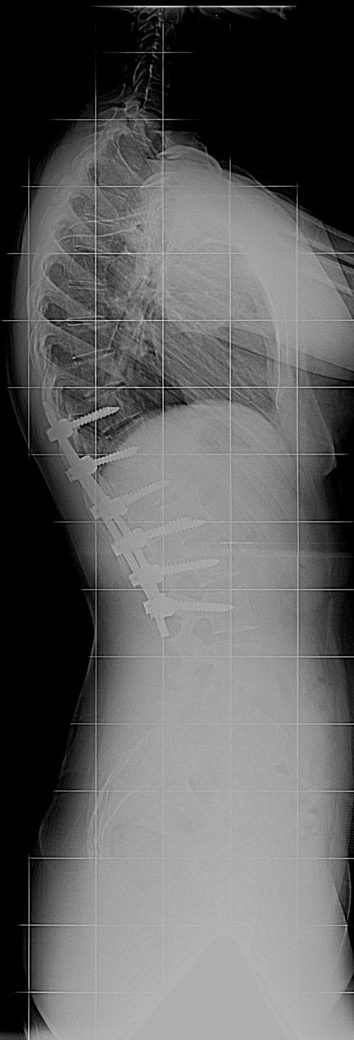

20 Yaşında Kadın Hasta

Boy: 171.3cm.

Kilo: 66kg

Rib hump lomber 10 derece

Ameliyat Öncesi

Ameliyat Sonrası